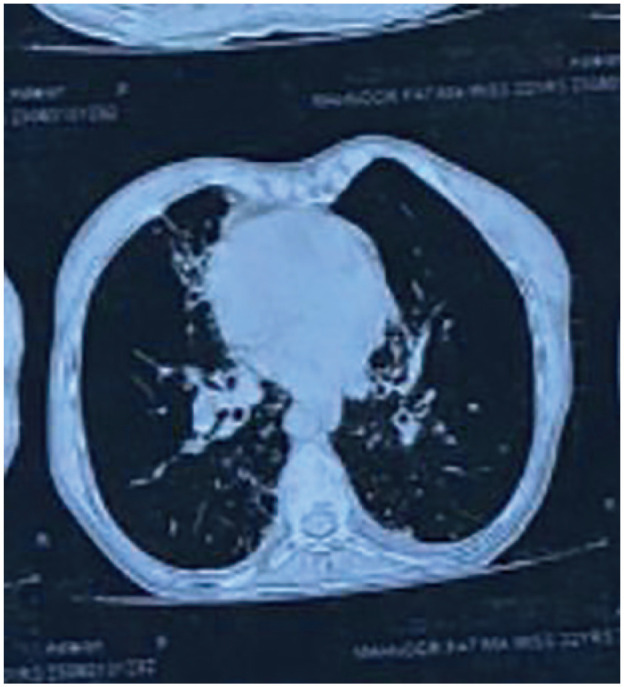

Case presentation: This case report discusses a 23-year-old female with Kartagener's syndrome, bronchiectasis, and cardiac involvement, who presented with shortness of breath, cough, and syncope. Notably, she received home oxygen therapy but became exhausted, leading to loss of consciousness. Clinical examination revealed prominent heart sounds and abnormal lung findings. Laboratory results indicated leukocytosis, and an ECG confirmed dextrocardia and cardiac abnormalities. Doppler studies identified mitral and tricuspid regurgitation along with severe pulmonary arterial hypertension. Antibiotics were administered for coagulase-negative Staphylococcus infection. The patient improved with a treatment regimen, including oxygenation and nebulization. Regular follow-up and patient education were emphasized.